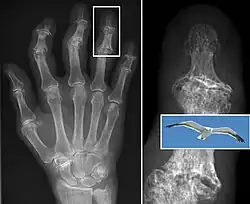

Diagnosis is made with reasonable certainty based on history and clinical examination.[52][53] X-rays may confirm the diagnosis. The typical changes seen on X-ray include: joint space narrowing, subchondral sclerosis (increased bone formation around the joint), subchondral cyst formation, and osteophytes.[54] Plain films may not correlate with the findings on physical examination or with the degree of pain.[55]

-

Severe osteoarthritis and osteopenia of the carpal joint and 1st carpometacarpal joint -

Bone (left) and clinical (right) changes of the hand in osteoarthritis